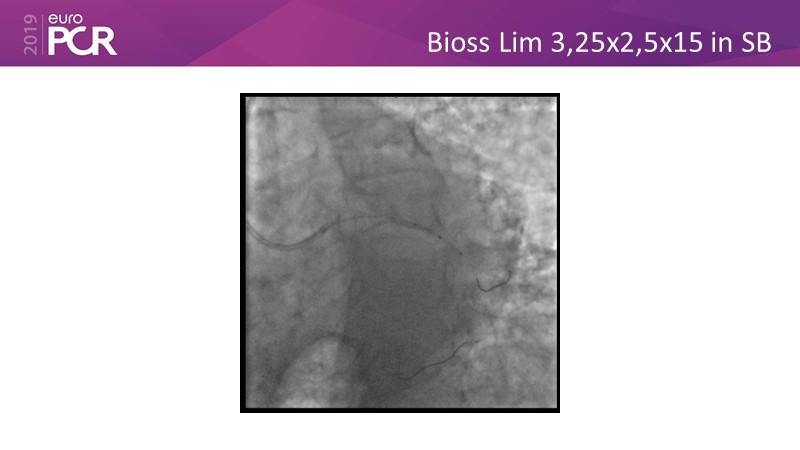

Distal left main stenosis: how to treat optimally with dedicated bifurcation stent BiOSS Lim C. Case-based session